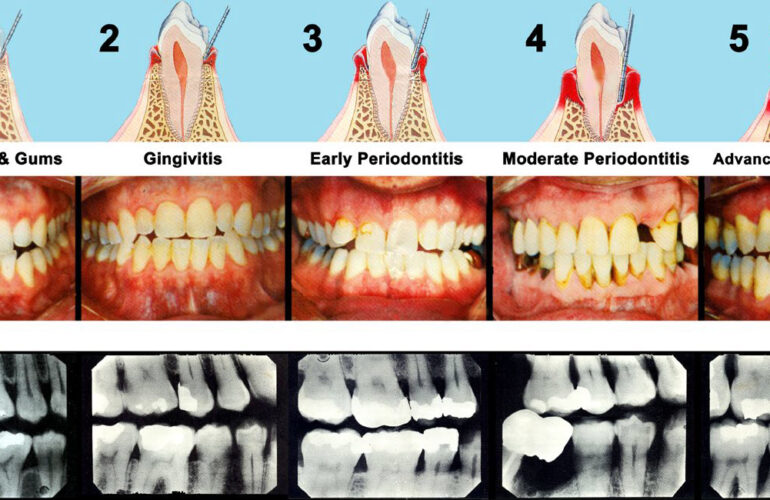

Get your dental health back on track with us

Are you looking for a dentist to give you special smile?